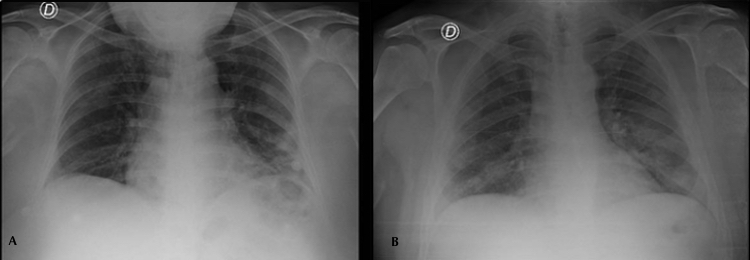

De los 11 pacientes COVID-19 positivos con hallazgos patológicos en la Rx, 8 (72%) se manifestaron como opacidades parcheadas en vidrio esmerilado y 3 (27%) como una asociación de infiltrados en vidrio esmerilado y consolidaciones (Fig. 1). En 8 (72%) pacientes las opacidades se distribuyeron en los lóbulos inferiores, dentro de los cuales 3 (27%) de ellos también mostraron compromiso del lóbulo medio. Solo 3 (27%) pacientes presentaron afectación. Se menciona además compromiso bilateral en 7 (63%) pacientes y unilateral en los restantes 4 (36%).

Se pudo estudiar la evolución radiológica de esta enfermedad en uno de los pacientes cuya evolución clínica fue tórpida, observándose en una radiografía inicial sutiles áreas parcheadas en vidrio esmerilado en campos pulmonares inferiores, las cuales fueron progresando hasta volverse coalescentes, difusas y consolidativas, llegando a afectar la mayor parte del parénquima pulmonar, asociándose además a derrame pleural. El paciente requirió intubación orotraqueal al décimo día de internación, sin lograr mejorar su cuadro clínico, y se constató su deceso 10 días más tarde (Fig. 2).